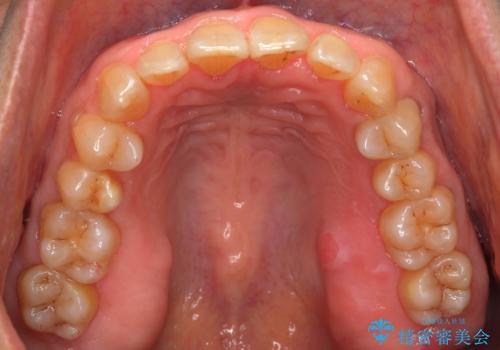

- 前歯のがたつきを主訴に来院。

右下の犬歯が歯ぐきが痩せて、歯肉退縮しておりそれを抜歯しました。

上の前歯はIPRを行なっています。

右下の犬歯の1本抜歯で最小限の抜歯で並べることができました。